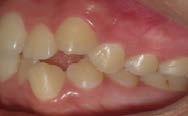

Paciente femenina de 15 años de edad que acudió a la Clínica de Ortodoncia Instituto Profesional Odontológico Contemporáneo (IPOC) en Saltillo, Coahuila, México. El motivo de su consulta fue que “quiero brackets porque sus colmillos están encimados”. Los estudios de rutina le fueron solicitados en la historia clínica SDCP. A la inspección clínica se observó paciente mesofacial, forma facial ovalada, con lado de compresión del lado derecho y lado de distracción del lado izquierdo, perfil recto, línea media facial y dental inferior no coincidían, tercio inferior aumentado, labios medianos e incompetencia labial (Figura 1).

El examen clínico intraoral reveló una clase I molar bilateral, caninos superiores en infraoclusión, por ende la clase canina no se puede clasificar, presencia de apiñamiento severo, rotaciones en premolares superiores e inferiores, línea media inferior desviada hacia el lado derecho 3.5 mm,

Figura 12. Antes vs. después.

Figura 12. Antes vs. después. (Continuación)

los caninos que se encontraban en infraoclusión terminan bajando a su posición y nos permiten engranar la clase I canina molar de ambos lados conservando la clase I molar bilateral, conservando también el perfil recto, la clase I esqueletal, el crecimiento neutro y manteniendo en norma la proyección incisal y la correcta posición de los labios.